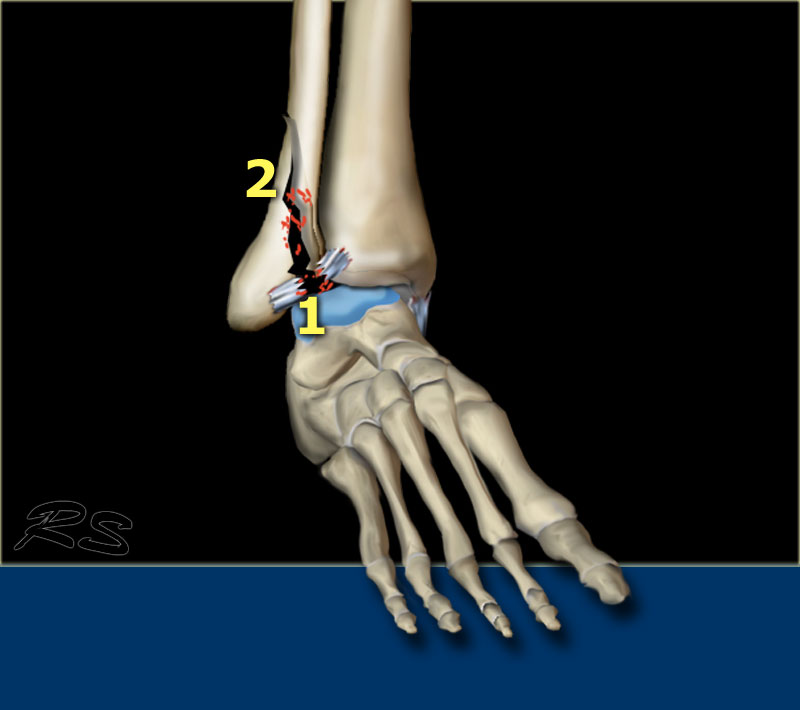

Stage 1-2

Giai đoạn 1 thường không thể nhìn thấy trên phim X-quang.

Điều chúng ta thường thấy là gãy xương chéo giai đoạn 2 qua khớp chày mác và chúng ta phải giả định rằng cũng có đứt dây chằng chày mác trước, tức là giai đoạn 1.

Các hình ảnh cho thấy gãy xương Weber B.

Đường gãy chéo là đặc trưng điển hình của Weber B và là kết quả của sự xoay ngoài của xương sên đẩy vào mắt cá ngoài cố định.

Gãy xương mắt cá thường bắt đầu ở phía trong tại mức vòm xương sên, nhưng cũng có thể bắt đầu cao hơn mức này vài centimet.

Stage 3-4

Giai đoạn 3 Sự dịch chuyển ra sau nhiều hơn của mảnh mắt cá ngoài do xương sên gây ra lực căng lên khớp chày mác sau dẫn đến đứt hoặc bong điểm bám của mắt cá sau.

Giai đoạn 4 Sự di chuyển ra sau thêm của xương sên sẽ gây ra căng thẳng cực độ ở phía trong và dây chằng delta sẽ hoặc bị đứt hoặc bị bứt ra khỏi mắt cá trong theo mặt phẳng ngang.

Các giai đoạn trong gãy xương Weber B hoặc tổn thương xoay ngoài-sấp theo phân loại Lauge-Hansen diễn ra theo chiều kim đồng hồ:

- Rupture of the anterior tibiofibular ligament

- Oblique fracture of the distal fibula

- Avulsion của mắt cá sau hoặc đứt dây chằng chày mác sau

- Avulsion của mắt cá trong hoặc đứt dây chằng bên trong